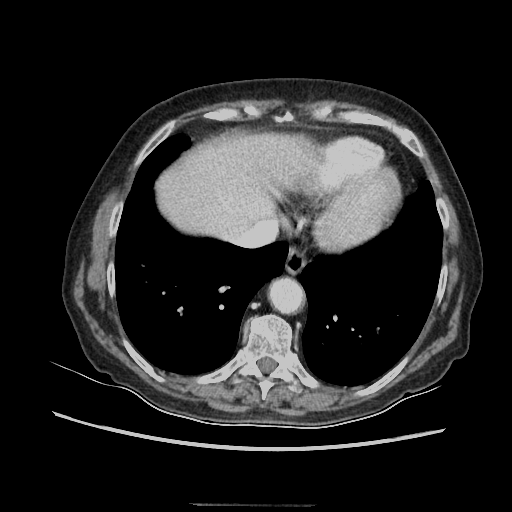

Generated VENOUS CT scan (A→B translation)

Full window (WL 1023.5, WW 4095 β†’ Low βˆ’1024, High +3071)

Mediastinum window (WL 40, WW 400 β†’ Low βˆ’160, High +240)